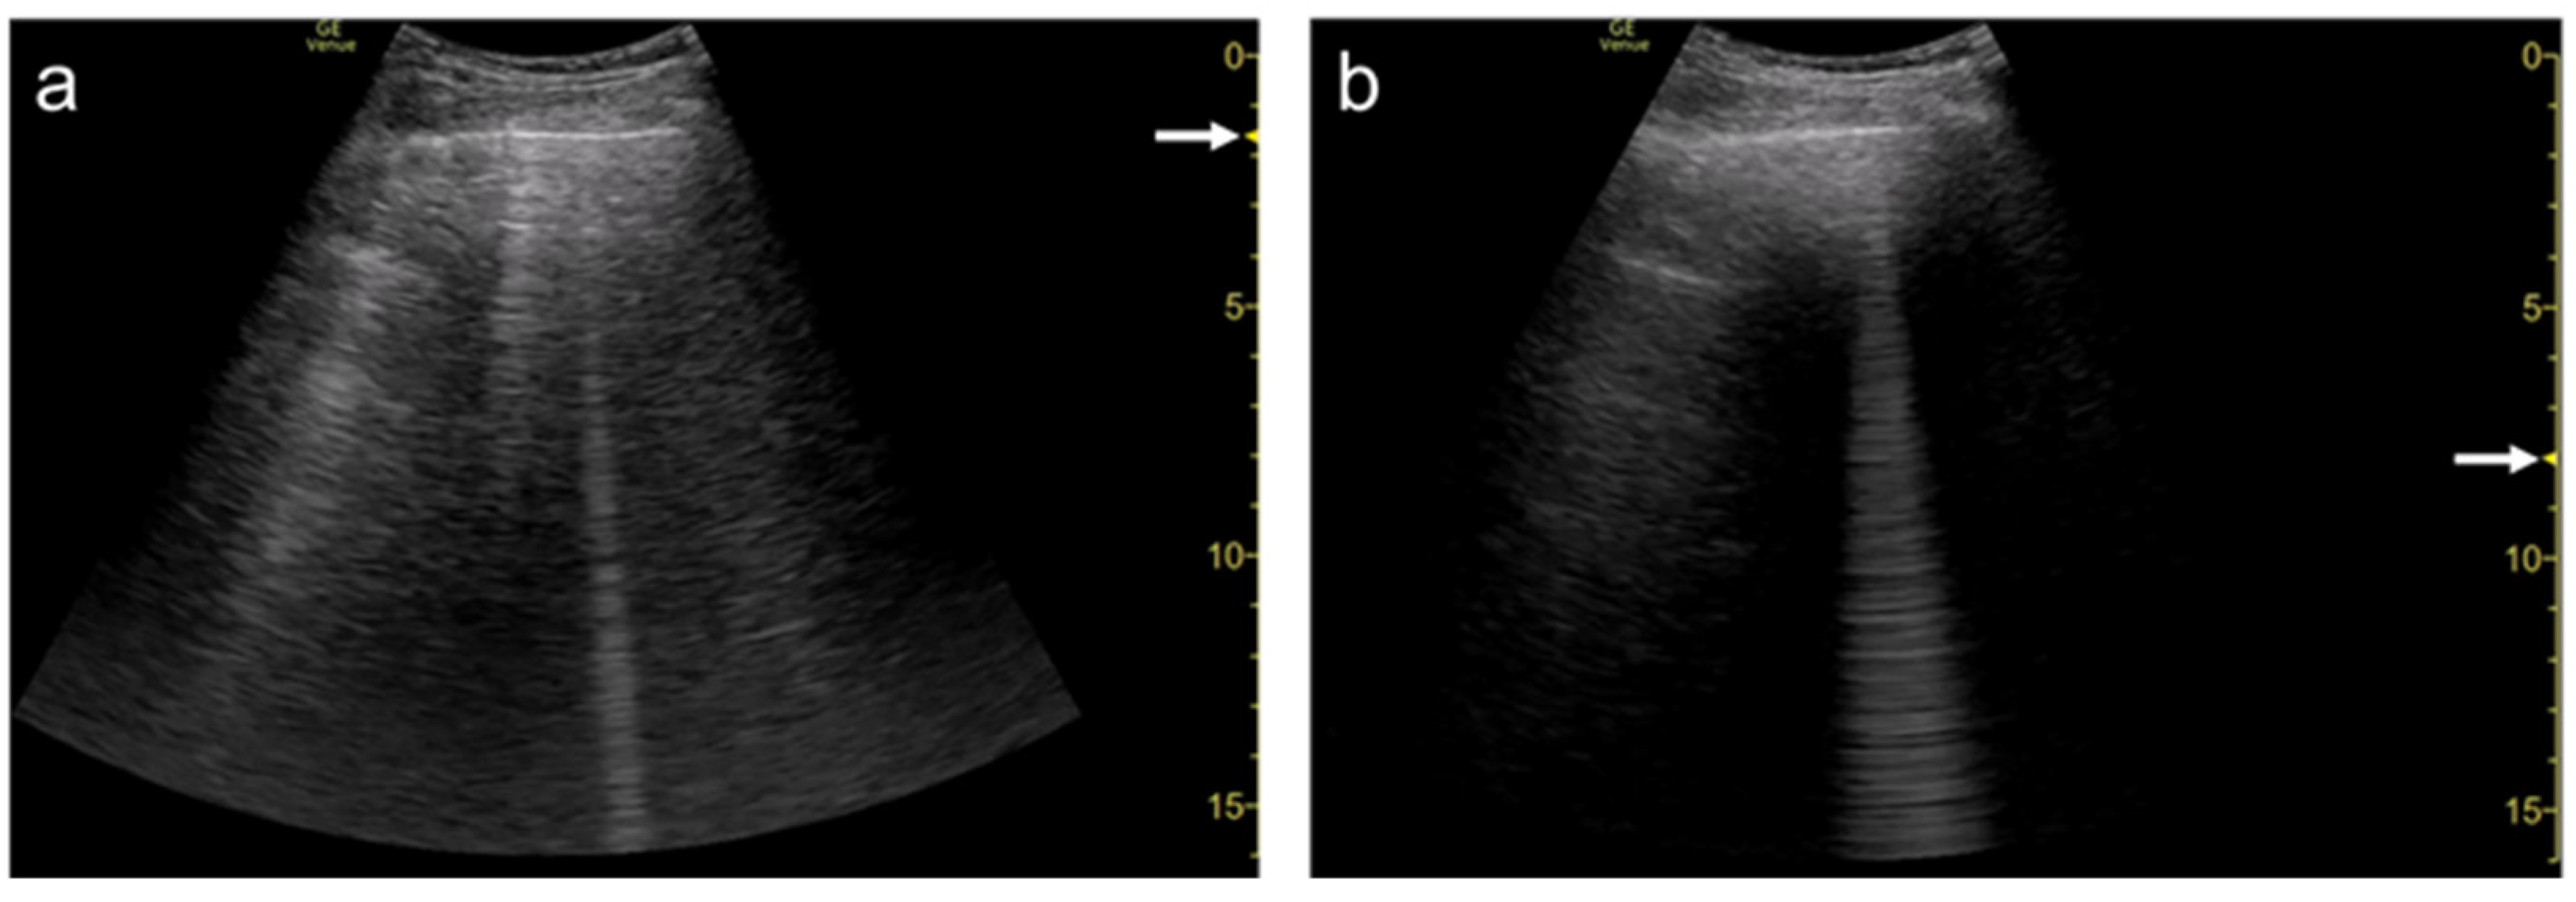

3.4. Selection of Transducers

3.5. Simple Educational Materials